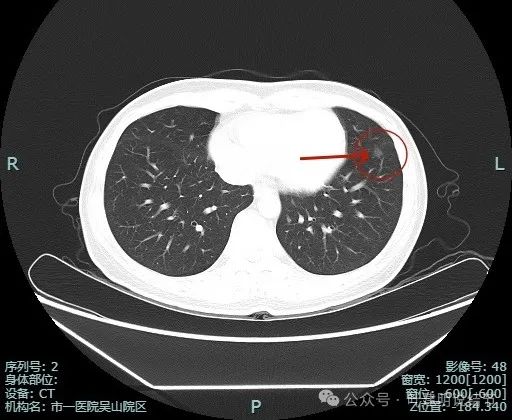

先看非薄层影像:

左肺淡磨玻璃结节,轮廓与边界较为清楚。

有微小血管走向病灶,而且病灶表面欠平滑。